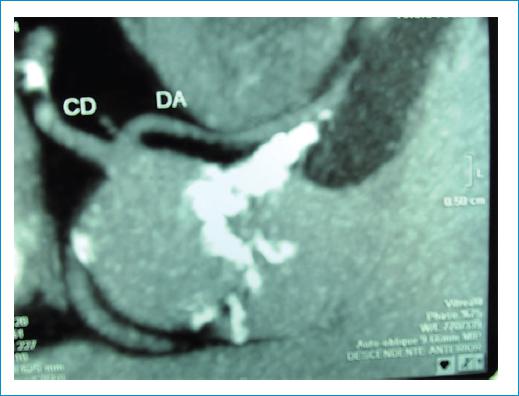

Figura 2 Angiotomografia coronaria en la cual resulta evidente el origen conjunto de la descendente anterior y coronaria derecha desde el seno de valsalva derecho. CD: coronaria derecha; DA: descendente anterior.

Se presenta el caso de un varón de 58 años con estenosis aórtica grave y válvula bicúspide, remitido para sustitución valvular. Como parte de su evaluación prequirúrgica se realizó una cinecoronariografía que reveló un origen anómalo de la arteria descendente anterior, la cual nace desde el seno coronario derecho, junto a la coronaria homónima (Fig. 1). Ante este hallazgo se solicitó una angiotomografía coronaria para definir el trayecto del vaso, precisándose el origen común de las arterias descendente anterior y coronaria derecha. La primera tenía un curso entre la raíz aórtica y la arteria pulmonar, y su recorrido subpulmonar, ingresando posteriormente en el tabique interventricular (tercio superior) a través de un curso transeptal. Así mismo, se observó el origen de la arteria circunfleja desde el mismo seno coronario, pero con un ostium independiente y un trayecto retroaórtico (Figs. 2-3). El origen anómalo de la arteria coronaria izquierda en el seno de Valsalva derecho tiene una prevalencia del 0,02-0,03%, resulta infrecuente su asociación con válvula aórtica bicúspide y existen pocos casos reportados. Como particularidad agregada, todas las arterias coronarias se originan en el mismo seno de Valsalva. Al paciente se le practicó reemplazo valvular con prótesis mecánica y baipás mamario a la descendente anterior. La evolución posoperatoria resultó libre de eventos.